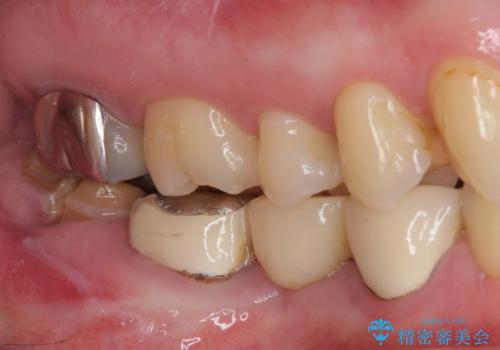

- 近医で奥歯が割れているので抜歯が必要と言われたとのことで来院された患者様です。

診断の結果、歯根が縦に破折しており抜歯が必要な状態でした。

抜歯してからインプラント埋入までには時間がかかるため、その間に下顎左右臼歯の金属のブリッジをオールセラミックへ変えていくこととしました。

目立つ部分の銀歯や気になる変色歯をまとめてきれいに仕上げることができました。